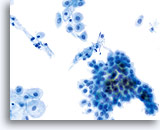

Postpartum

HSIL in a postpartum sample. Note the increased N/C ratio and abnormal chromatin in the HSIL cells as compared to the parabasal cells, apparent even at low magnification.

20X